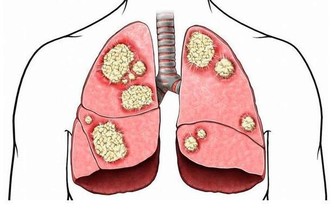

腎虛指腎臟精氣陰陽不足。腎虛的種類有很多,其中最常見的是腎陰虛,腎陽虛。

腎虛的症狀:腎陽虛的症狀為腰酸、四肢發冷、畏寒,甚至還有水腫,為“寒”的症狀,性功能不好也會導致腎陽虛;

腎陰虛的症狀為“熱”,主要有腰酸、燥熱、盜汗、虛汗、頭暈、耳鳴等。現代科學證明,當人發生腎虛時,無論腎陰虛還是腎陽虛,都會導致人的免疫能力的降低,有更多的證據表明,腎虛發生時,腎臟的免疫能力降低,而腎臟的微循環系統亦會發生阻塞,腎絡呈現不通。所以對於腎虛的治療應防治結合。